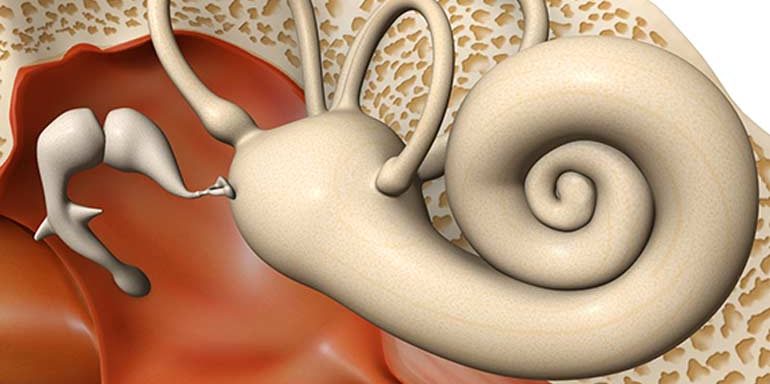

Kulak iltihabı orta kulak ve dış kulak iltihabı olarak ikiye ayrılır. Orta kulak iltihabı ya da otitis media, orta kulakta genellikle bir bakteri ya da virüs ile oluşan enfeksiyonlardır. En önemli belirtisi kulak ağrısıdır. Orta kulak iltihabı eğer tedavi edilmez ise kişide işitme kaybına neden olabilmektedir. Orta kulak iltihabı, daha çok, soğuk algınlığı, grip, alerji…

- Otitis Media: Orta kulak iltihabı olarak bilinir. Kulakta ağrı, işitme kaybı, basınç hissi gibi belirtilerle kendini gösterir.

- Otitis Eksterna: Dış kulak yolu iltihabıdır. Kulak kepçesi ve dış kulak yolu bölgesinde ağrı, kaşıntı, kızarıklık gibi belirtiler görülür.

- İşitme Kaybı: Farklı nedenlere bağlı olarak gelişen işitme kaybı, kulak hastalıklarının bir sonucu olabilir.

- Meniere Hastalığı: İç kulakta denge sorunlarına yol açan bir durumdur. Baş dönmesi, işitme kaybı ve kulak çınlaması görülebilir.

- Kulak Çınlaması (Tinnitus): Kulakta çınlama, uğultu veya zil sesi gibi algılanan bir durumdur. Çeşitli sebeplerle ortaya çıkabilir.